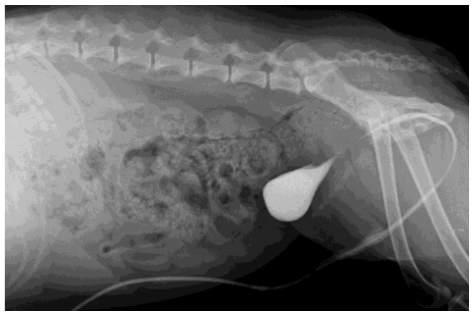

Após aproximadamente 15 dias em que o paciente permaneceu com catéter uretral fixado, foi realizado um novo exame radiográfico contrastado, em que os achados foram similares ao primeiro realizado, observando ainda a presença de um ponto de extravasamento de contraste em topografia de uretra prostática.

Com isso, foi indicada a realização de um novo procedimento cirúrgico, desta vez o de prostatectomia e anastomose uretrovesical ( Prostatectomia parcial: Ressecção cuidadosa da porção da próstata e da uretra gravemente lesada.

Após o procedimento, o paciente apresentou boa recuperação, sem complicações pós-cirúrgicas, com bom controle de dor e mantendo a sonda uretral por 7 dias pós-procedimento, para garantir uma boa cicatrização da região.

Após os 7 dias, foi realizada a última radiografia contrastada, que não evidenciou sinais de extravasamento de contraste e confirmou a cicatrização do ponto de ruptura.